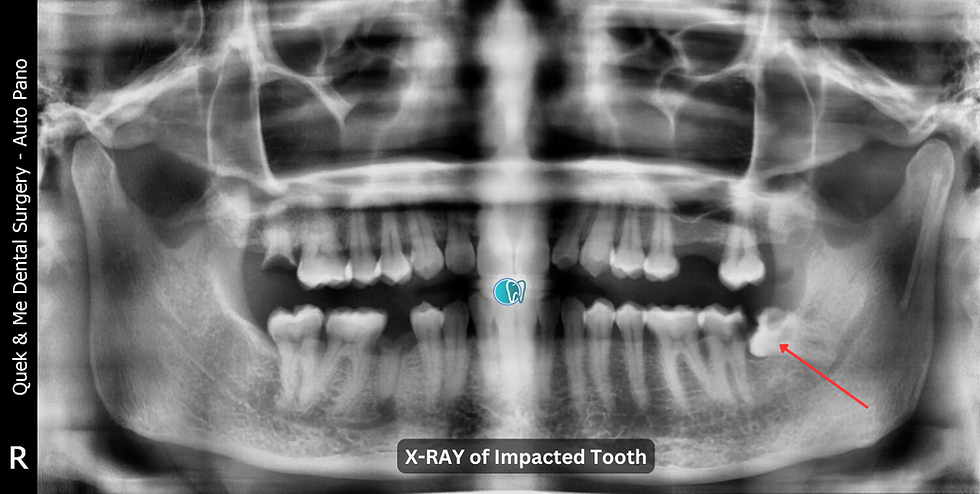

Surgical Removal of Impacted Tooth #38

Patient presents with pain and swelling, requesting removal of tooth #38. Tooth #38 is impacted with long thin roots and bulbous apices, closely contacting the inferior dental nerve (IDN). Tooth #37 also shows signs of caries.

Tooth #38: Impacted with long thin roots and bulbous apices, very tender to percussion (TTP), carious to the pulp, and in close proximity to the IDN. Mobility within normal limits.